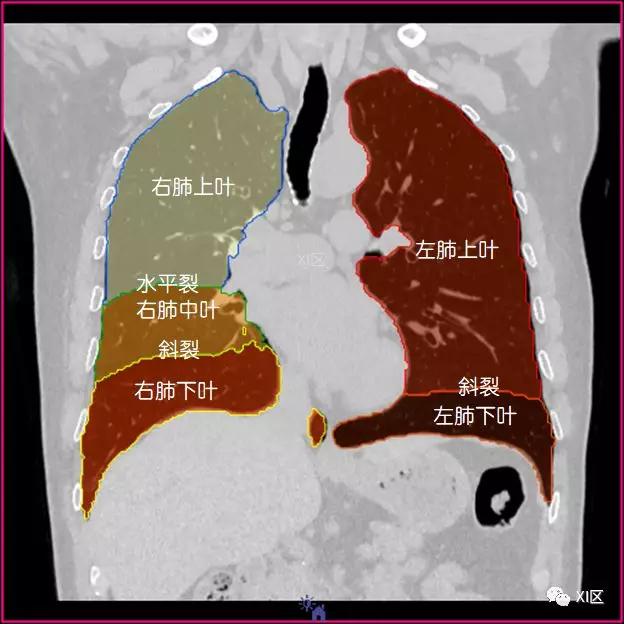

肺的分叶

左肺借斜裂成上、下两叶;右肺借斜裂和水平裂成上、中和下叶三叶。

冠状位